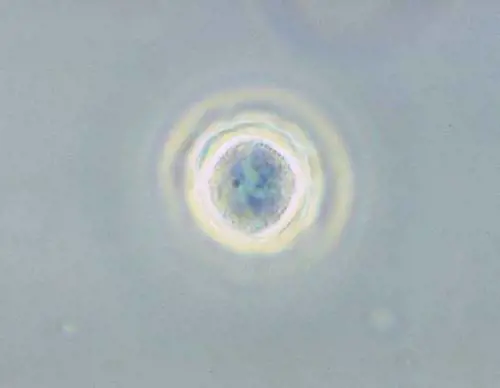

Un parassita nella cornea la rende quasi cieca